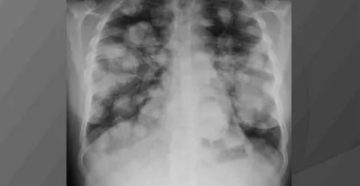

Как выявить метастазы в легких. КТ и рентгенологические признаки Компьютерная томография — один из самых…